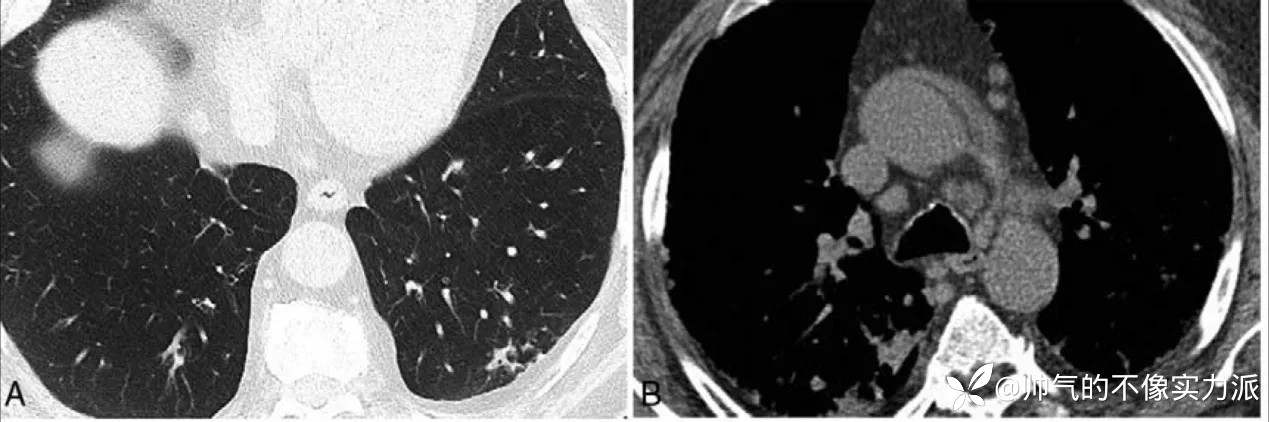

2018 年有个案报道 59 岁男性有 COPD、糖尿病、溃疡性肠炎史,间断口服激素,因干咳、低热与进行性呼吸困难住院,入院 CT 示左下肺少许簇状小结节,伴轻微的支气管周围实变(图 1A)与纵膈淋巴结轻度肿大(图 1B)[7]。

图 1 患者入院时 CT

图片来源:参考文献 7